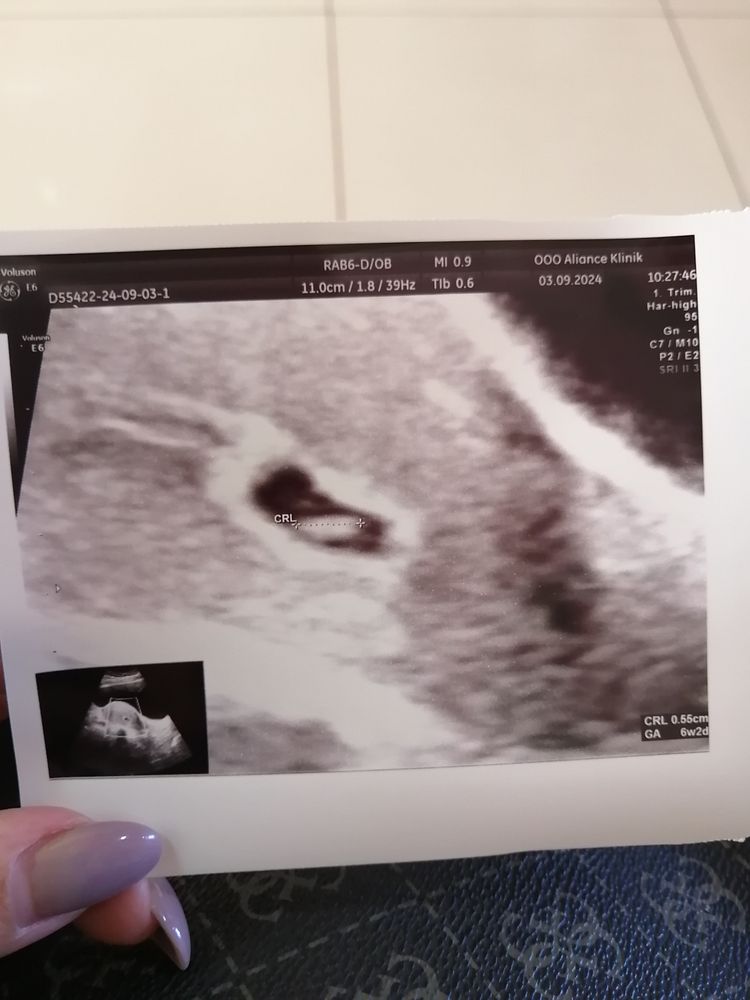

Сегодня 27дпп была на УЗИ, плодное яйцо в матке-9мм, жм-2,9 ктр-5,4мм по сроку 6 нед 2дн, ❤️ 110 ударов врач сказала только начало биться сердечко ещё разгонится. Сделали фото. Следующий приём на 16 сентября. Я так рада🥹как будто это все не со мной происходит.